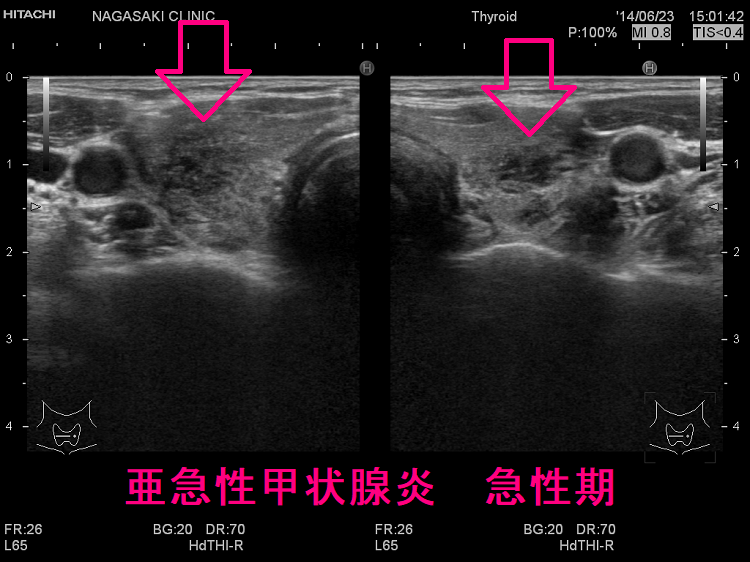

下は亜急性甲状腺炎の超音波(エコー)画像で、炎症の強い部分は黒く、エラストグラフィーでは青くなります。